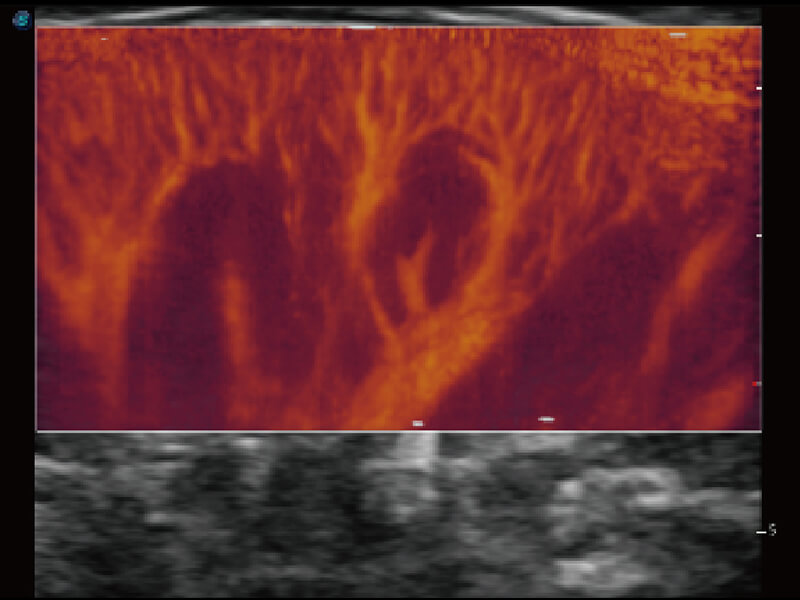

Micro F 显微血流成像 明察秋毫